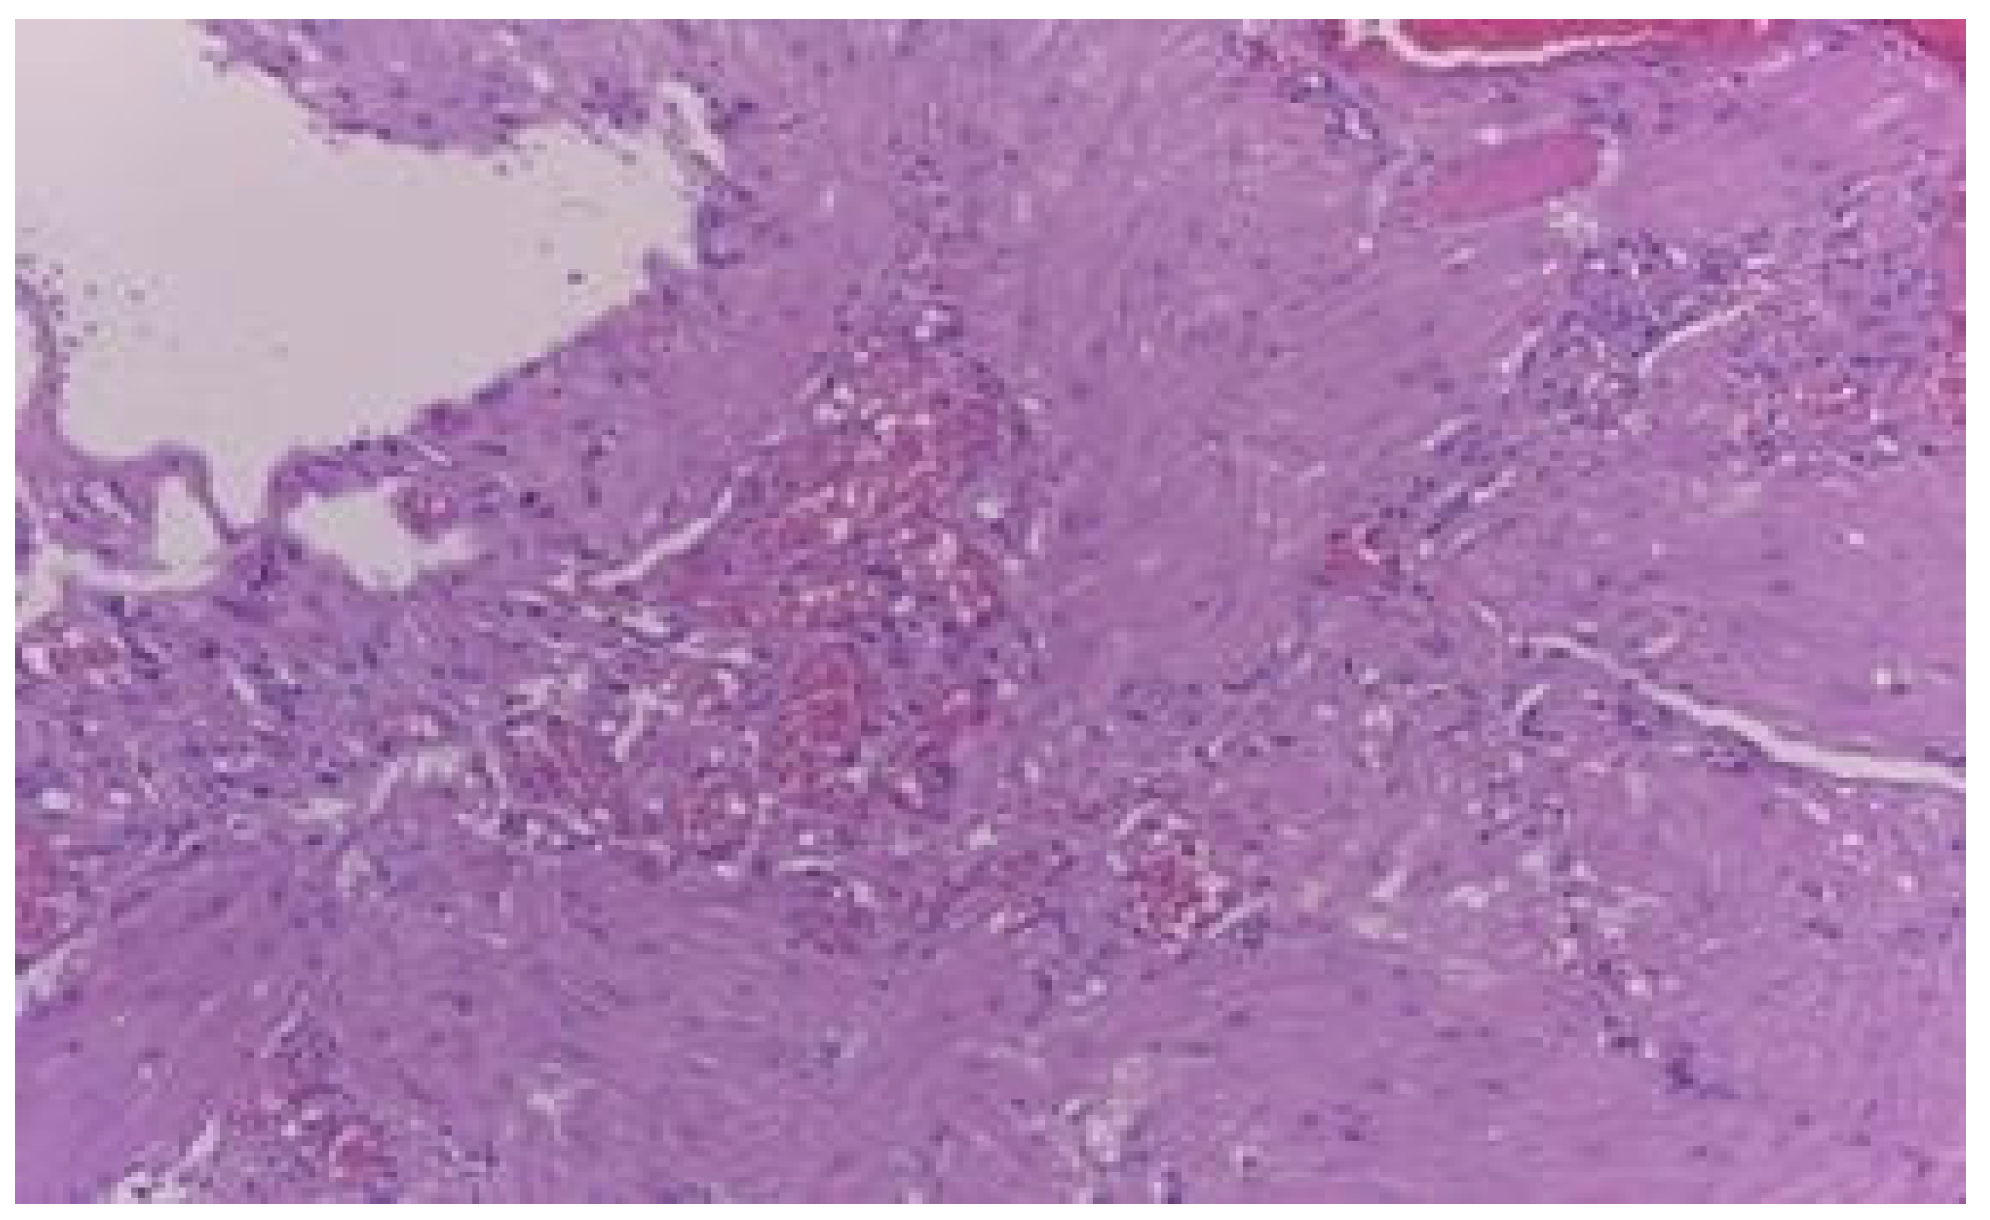

- This observation of inverse proportionality between the uterine thickness and the risk of rupture/dehiscence of the scar seems to be correlated with the histopathological features of the cesarean section scar.